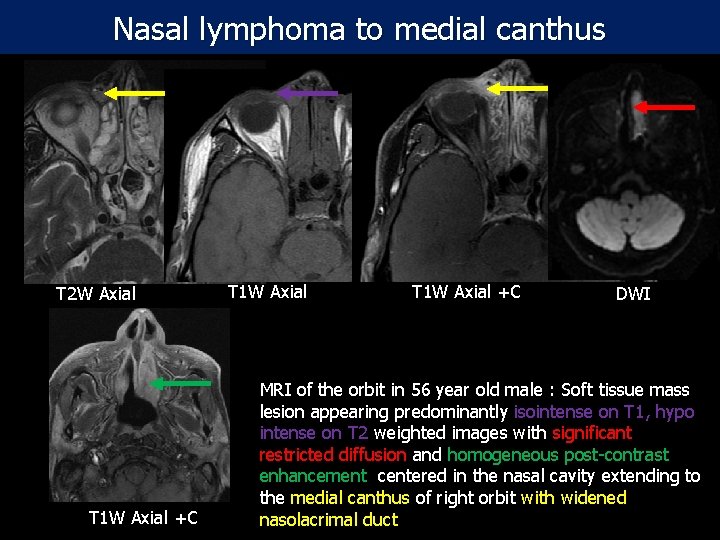

Nasal lymphoma to medial canthus T 2 W Axial T 1 W Axial +C DWI MRI of the orbit in 56 year old male : Soft tissue mass lesion appearing predominantly isointense on T 1, hypo intense on T 2 weighted images with significant restricted diffusion and homogeneous post-contrast enhancement centered in the nasal cavity extending to the medial canthus of right orbit with widened nasolacrimal duct